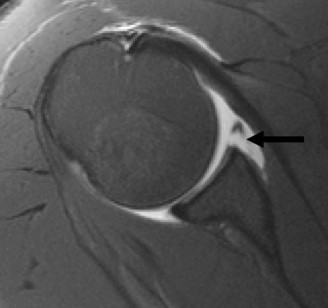

Identify the muscles that compose the force couples in the transverse and coronal planes? CASE 3 A 35-year-old male has had left shoulder pain for 4 months, ever since a low-speed motor vehicle accident (MVA). Physical examination demonstrates preserved range of motion but pain and some weakness with Jobe’s testing. His imaging is shown in Figure 2–8.

Figure 2–8_Reproduced with permission from Stadnick ME. _Partial Rotator Cuff Tears. MRI Web Clinic. 2007 (Apr).

What is the most likely diagnosis?

The correct answer is (A). These are best diagnosed on an MRI as seen in the imaging provided; addition of intra-articular contrast can further improve this study. Answer B, full-thickness rotator cuff tear, is incorrect as the bursal side of the tendon can be seen to be in continuity. Answer C, a SLAP lesion, will be visualized as a labral tear on a coronal MRI and will be found at the biceps root. Answer D, an ALPSA lesion, will be most clearly seen on an axial MRI. It is a variant of a Bankart lesion where the labrum is displaced medially and inferiorly rolling down the glenoid neck underneath the periosteum.

MRI remains the most popular imaging modality for diagnosing rotator cuff tears. Normal rotator cuff tendon appears dark on both T1 and T2 sequences. Tears may be noted as being full-thickness, articular-sided, bursal-sided, or intrasubstance. They are visualized as a disruption in the regular contour of the tendon and increased signal intensity on T2 sequences. Occasionally, an MR arthrogram may provide additional information regarding a cuff tear, although this is not routinely ordered.

What MRI sequence and plane is best for viewing supraspinatus rotator cuff tears?

The correct answer is (D). T2 sequence causes most soft tissues, including muscle and tendon, to appear dark and inflammation, such as at the site of a tear, to appear bright. This means that if there is a rotator cuff tear, there will be a bright spot along the course of the dark rotator cuff tendon. This is easiest to pick out in the coronal plane because the tendon runs in this plane, allowing one to view the entire supraspinatus tendon and tear in one cut.